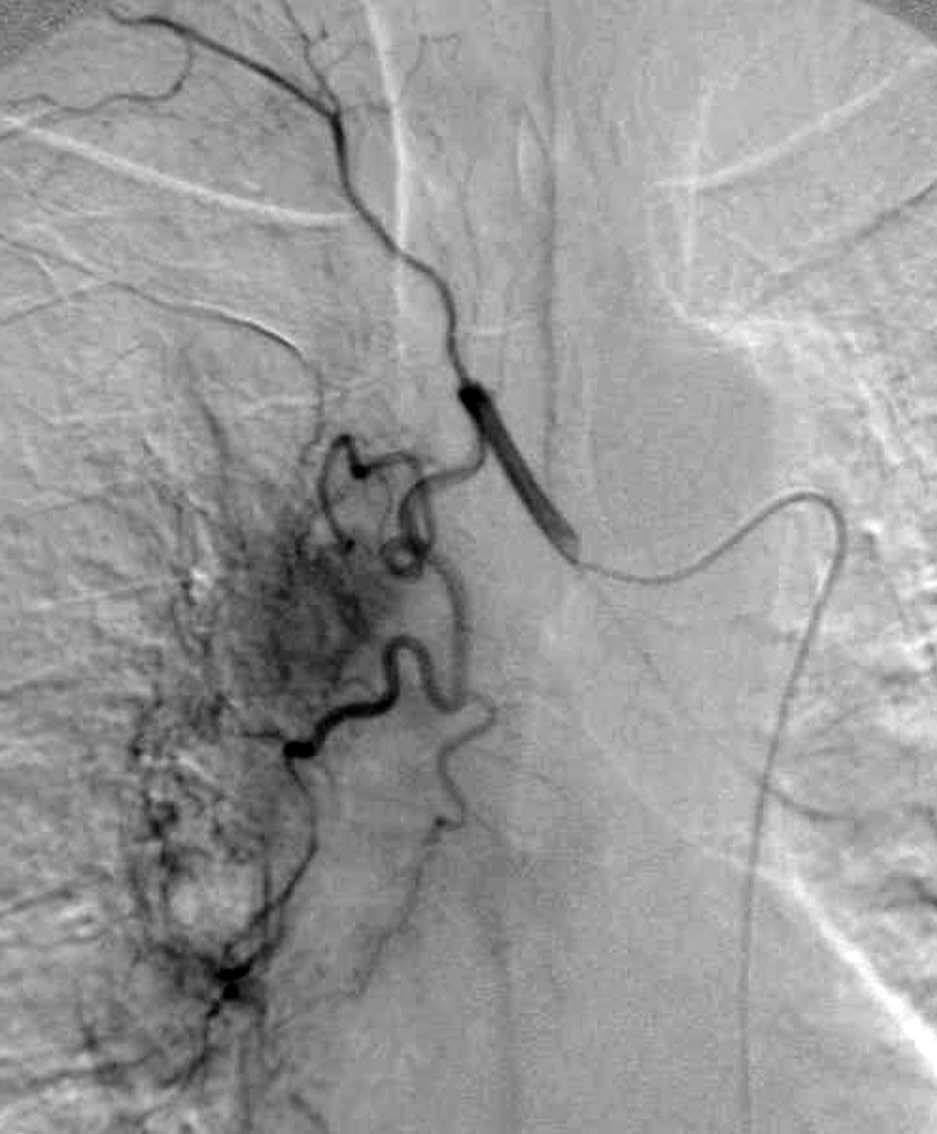

Una ventaja adicional de la TCMC es la capacidad de realizar, como parte del estudio de extensión, una angiografía TC (angioTC) en los tumores de localización central candidatos a cirugía y, fundamentalmente, en aquellos pacientes con hemoptisis que podrían ser subsidiarios de embolización terapéutica. El estudio vascular permite tener un excelente mapa para la cirugía, que ayuda enormemente al cirujano a la hora de planificar la intervención (fig 8). En los pacientes con hemoptisis amenazante, la demostración de una arteria sistémica hipertrófica sirve de guía para la arteriografía y subsecuente terapia endovascular (fig. 9).

Fig. 9.--Hemoptisis masiva secundaria a neoplasia de pulmón. (A) Corte axial con contraste que muestra el origen de la arteria bronquial derecha en la aorta descendente. (B) Reconstrucción de volumen en la que se pone de manifiesto la localización exacta de la arteria bronquial derecha hipertrófica y su exquisita correlación con la angiografía selectiva (C).